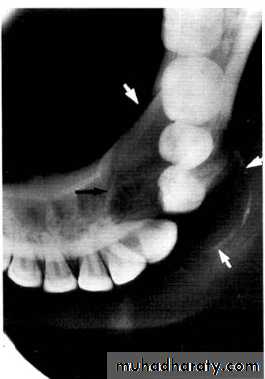

Central giant cell granuloma*A relatively uncommon, non- neoplastic mass in the jaws (intraosseous) producing an expansile radiolucent soap bubble appearance.

*Age; <20 years. Female > Male.

*Teeth are vital, with some root resorption & migration of teeth.

Multilocular appearance, expansion (arrowed) and considerable displacement of the adjacent teeth.

Buccal and lingual expansion (arrowed) and the undulating cortical border.